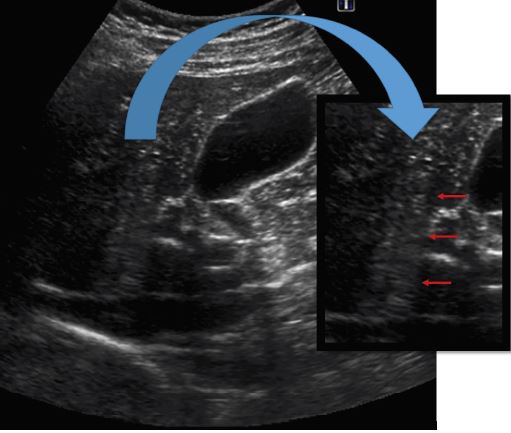

La Hamartomatosis Biliar Múltiple es una entidad congénita, descrita por Von Meyenburg en 1918, que se incluye dentro de las enfermedades fibropoliquísticas del hígado, donde también destacan la enfermedad de Caroli, la enfermedad poliquística A.D.o la fibrosis hepática (fig.1). La enfermedad se debe a un fallo en la involución de los conductos biliares terminales embrionarios, lo que condiciona la aparición de hamartomas biliares o complejos de Von-Meyenburg, que no son más que dilataciones quísticas de estructuras ductales perifericas, en el seno de un estroma fibroso con poca vascularización(fig.2).

Macroscópicamente, vemos un hígado con pequeños nódulos blanquecino- amarillentos o blanquecino-grisáceos, que se distribuyen de manera difusa por toda su superficie, aunque son algo más frecuentes en áreas subcapsulares. El tamaño varía de 1 a 15 mm., con una media de unos 10mm. y debido a su etiología, no es infrecuente que se asocien con otros quistes en hígado, riñones o incluso pancreas.

Microscópicamente: se objetivan las dilataciones de los ductos terminales con morfologías redondeadas o irregulares, que NO COMUNICAN con la vía biliar y se encuentran recubiertos por una fina capa de células cuboidales. Pueden contener algo de bilis- cristales de colesterol y aunque puede verse algún vaso aislado (frecuentemente escleroso), la vascularización es escasa.